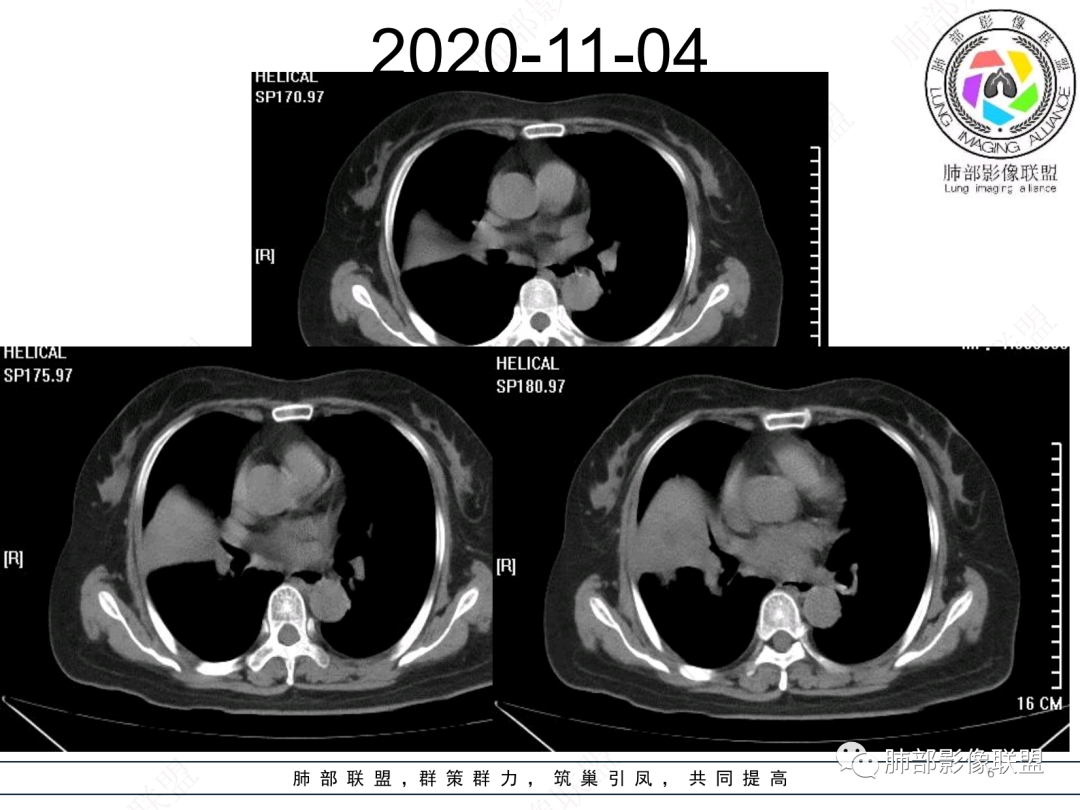

老年女性患者,慢性病程,两次活检均提示炎性病变,胸部CT:右肺中叶大片实变密度影,边界尚清楚,部分收缩,部分膨隆,内部有低密度坏死,坏死边界清楚,无明显结节感,无分割,总体考虑炎性病变,机化性肺炎,NTM,慢性肺脓肿,鉴别:恶性,腺癌

右肺中叶大片实变,内见大片的坏死,中叶外侧段支气管阻塞,相邻胸膜增厚,间隔约四个月后复查,发现低密度坏死内可见气泡影,老年人,反复迁延不愈的病变要考虑恶性,首先考虑腺癌伴感染。鉴别慢性脓肿。

老年女性,慢性病史,炎性指标稍高,肿标正常,右中下肺大片实变,跨叶生长,边界清,收缩力差,膨隆生长为主,支气管杵状截断,均匀强化,其内坏死边界清,可见悬浮气泡,整体观察,病灶膨隆生长为主,邻近肺野无播散灶,形态单一,尽管慢性病史,影像不支持OP和TB,支气管截断呈杵状,肿标正常,均匀强化,虽是高龄患者,诊断恶性肿瘤有点牵强,综和分析,首选炎性病变放线菌感染,其次考虑低度恶性占位炎机母。

这个病灶中叶、下叶都有

坏死腔是连通的

然后中叶与下叶的坏死腔病灶是相通的,病灶是跨叶的,胸膜糊墙为主。

南边:跨叶、楔形/边缘平直、支气管壁无破坏/连续/局部无膨大、实变区肺动脉走形自然、实性部分均匀、延迟强化、坏死腔内壁光滑/内壁强化环/近端与支气管相通,这些点均支持炎性。所以综合分析:符合炎性。